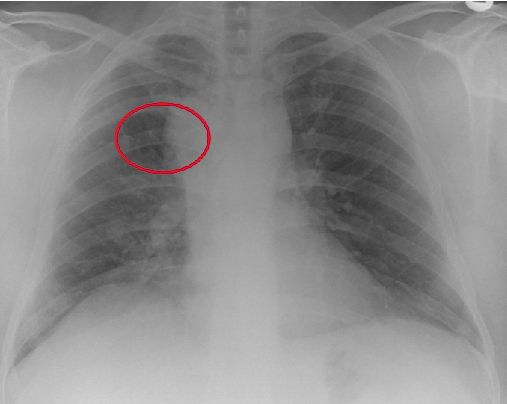

Figura 4.

Signos radiológicos de la hernia pulmonar. La radiografía muestra una lesión mediastinal en el ángulo traqueobronquial derecho. “Lucent lung” sing.

Editado de: Zia Z, Bashir O, Ramjas GE, Kumaran M, Pollock JG, Pointon K. Intercostal lung hernia: radiographic and MDCT findings. Clin Radiol 2013;68(7):e412-7. http://dx.doi.org/10.1016/j.crad.2012.11.024